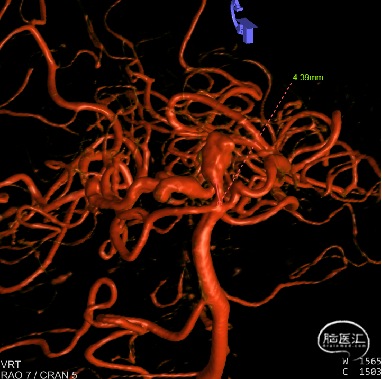

CT(CTA)检查提示:右颈内动脉C7段大小约3.6×3.8×3.6mm及基底动脉远端动脉瘤形成大小约9.7×7.6×9.3mm。

DSA:右侧P1段一6.8*9.7mm不规则囊状突起动脉瘤,远端P2段呈螺旋状蛇形动脉瘤改变。

右侧颈内3D

动脉瘤参数:

动脉瘤大小为6.8*9.7mm,瘤颈宽4mm

载瘤动脉(颈内动脉)近端狭窄处为1.7mm,近端末狭窄处为1.4mm,远端为2.4mm。